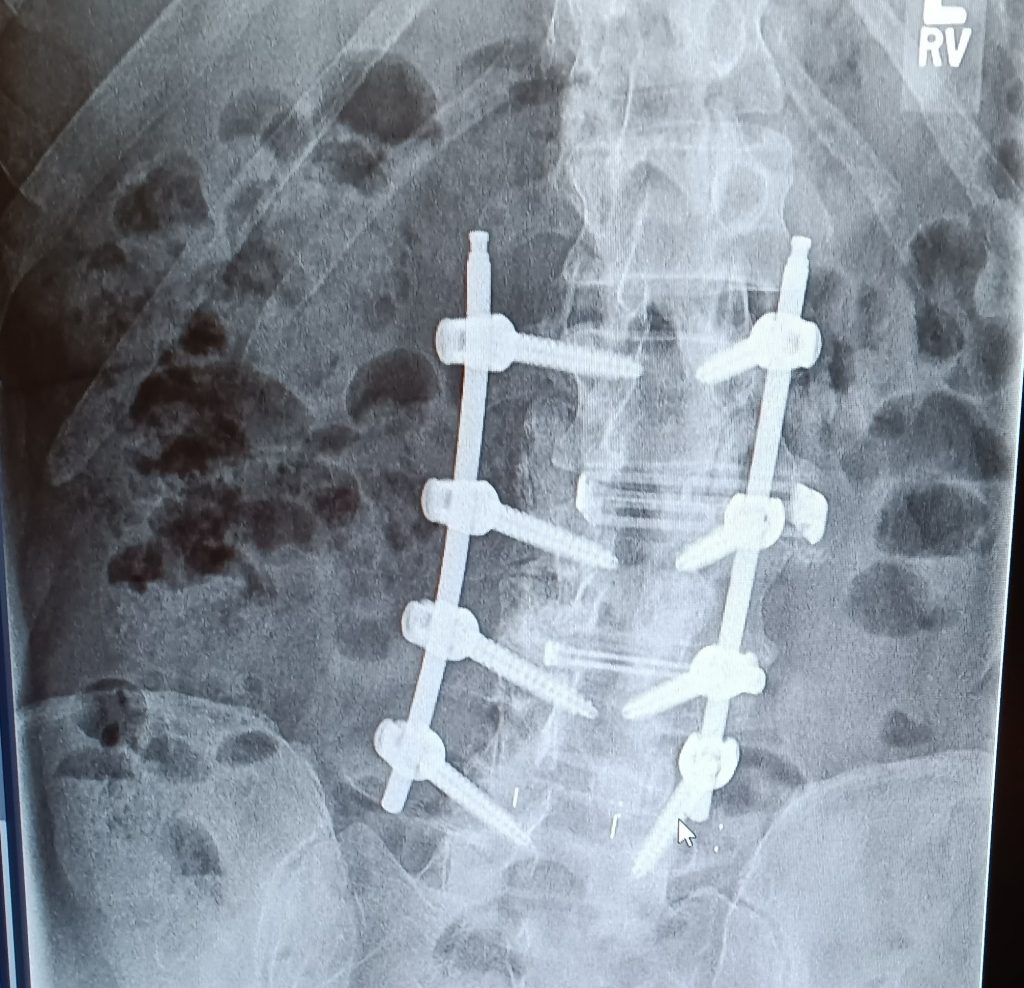

Dr Qureshi strongly suggested spinal fusion of the L4-L5 area of my spine. Not knowing what all that entailed I asked many questions which he easily answered for me. He explained how the minimal invasive surgery works compared to traditional surgery. He even reviewed with me all the images of my spine pointing out what he saw and explained the process to correct it. I’m still amazed as to how just a few small holes in my back and one larger one in my side allowed him to put all surgical equipment in to do the fusion work.